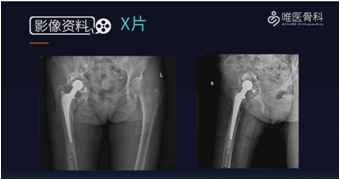

影像学检查:术前X线片提示右侧人工髋关节置换术后改变,髋臼假体松动。

诊断:右髋关节置换术后;无菌性松动。

取出髋臼假体:去除髋臼周围的瘢痕组织,显露整个髋臼缘,取出已松动的全聚乙烯臼杯。然后用刮勺刮除纤维膜,充分显露骨床,评估残余骨量。根据髋臼内侧壁、前后壁及臼顶的骨缺损程度以及髋关节中心上移程度确定骨缺损分型。本病例髋臼骨缺损分型为:Paprosky ⅡC型。